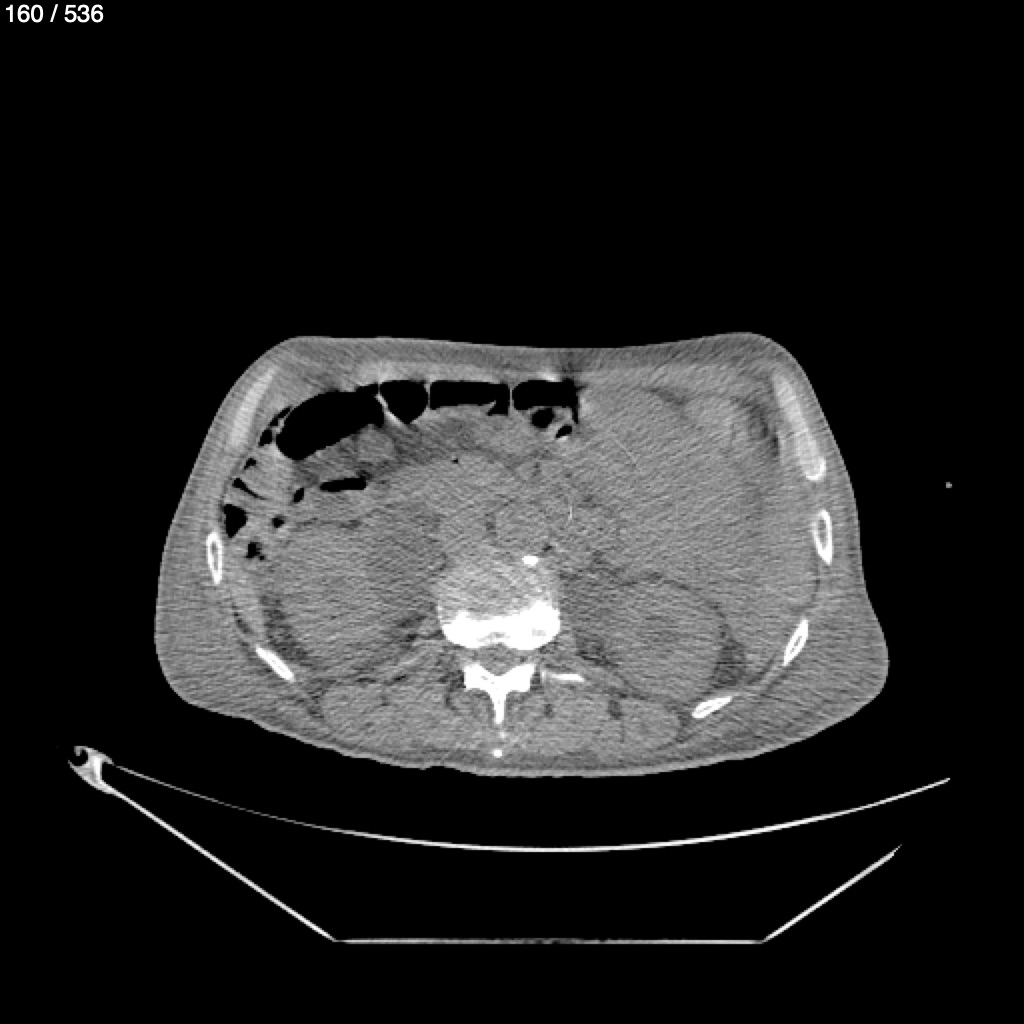

Angel Villalobos Palomeque 73 A - T.C Abdomen Simple